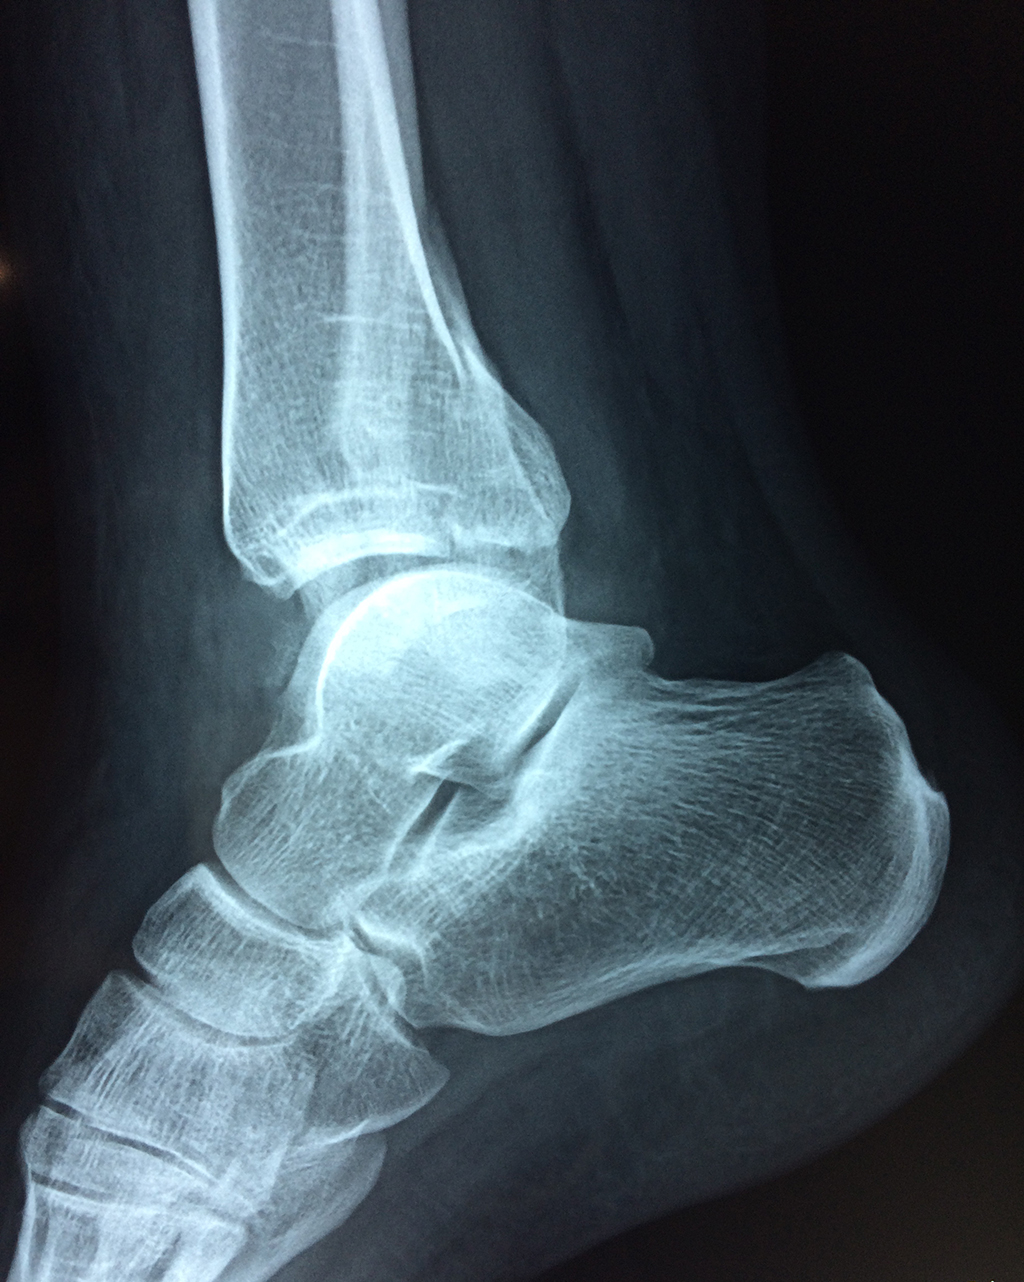

Una fractura de tobillo es la rotura de uno o más de los huesos del tobillo. Estas fracturas pueden ser:

- Parciales (el hueso está sólo parcialmente fisurado, no del todo).

- Completas (el hueso está perforado y está en 2 partes).

- Producirse en uno o ambos lados del tobillo.

Algunas fracturas de tobillo pueden requerir cirugía si:

- Los extremos de los huesos están desalineados entre sí (desplazados).

- La fractura se extiende hasta la articulación del tobillo (fractura intra-articular).

- Los tendones o ligamentos (tejidos que sujetan los músculos y los huesos entre sí) están rotos.

- El médico cree que sus huesos probablemente no sanen apropiadamente sin cirugía.

- El médico considera que la cirugía puede permitirle una recuperación más rápida y confiable.

- En los niños, la fractura involucra la parte del hueso del tobillo donde el hueso está creciendo.